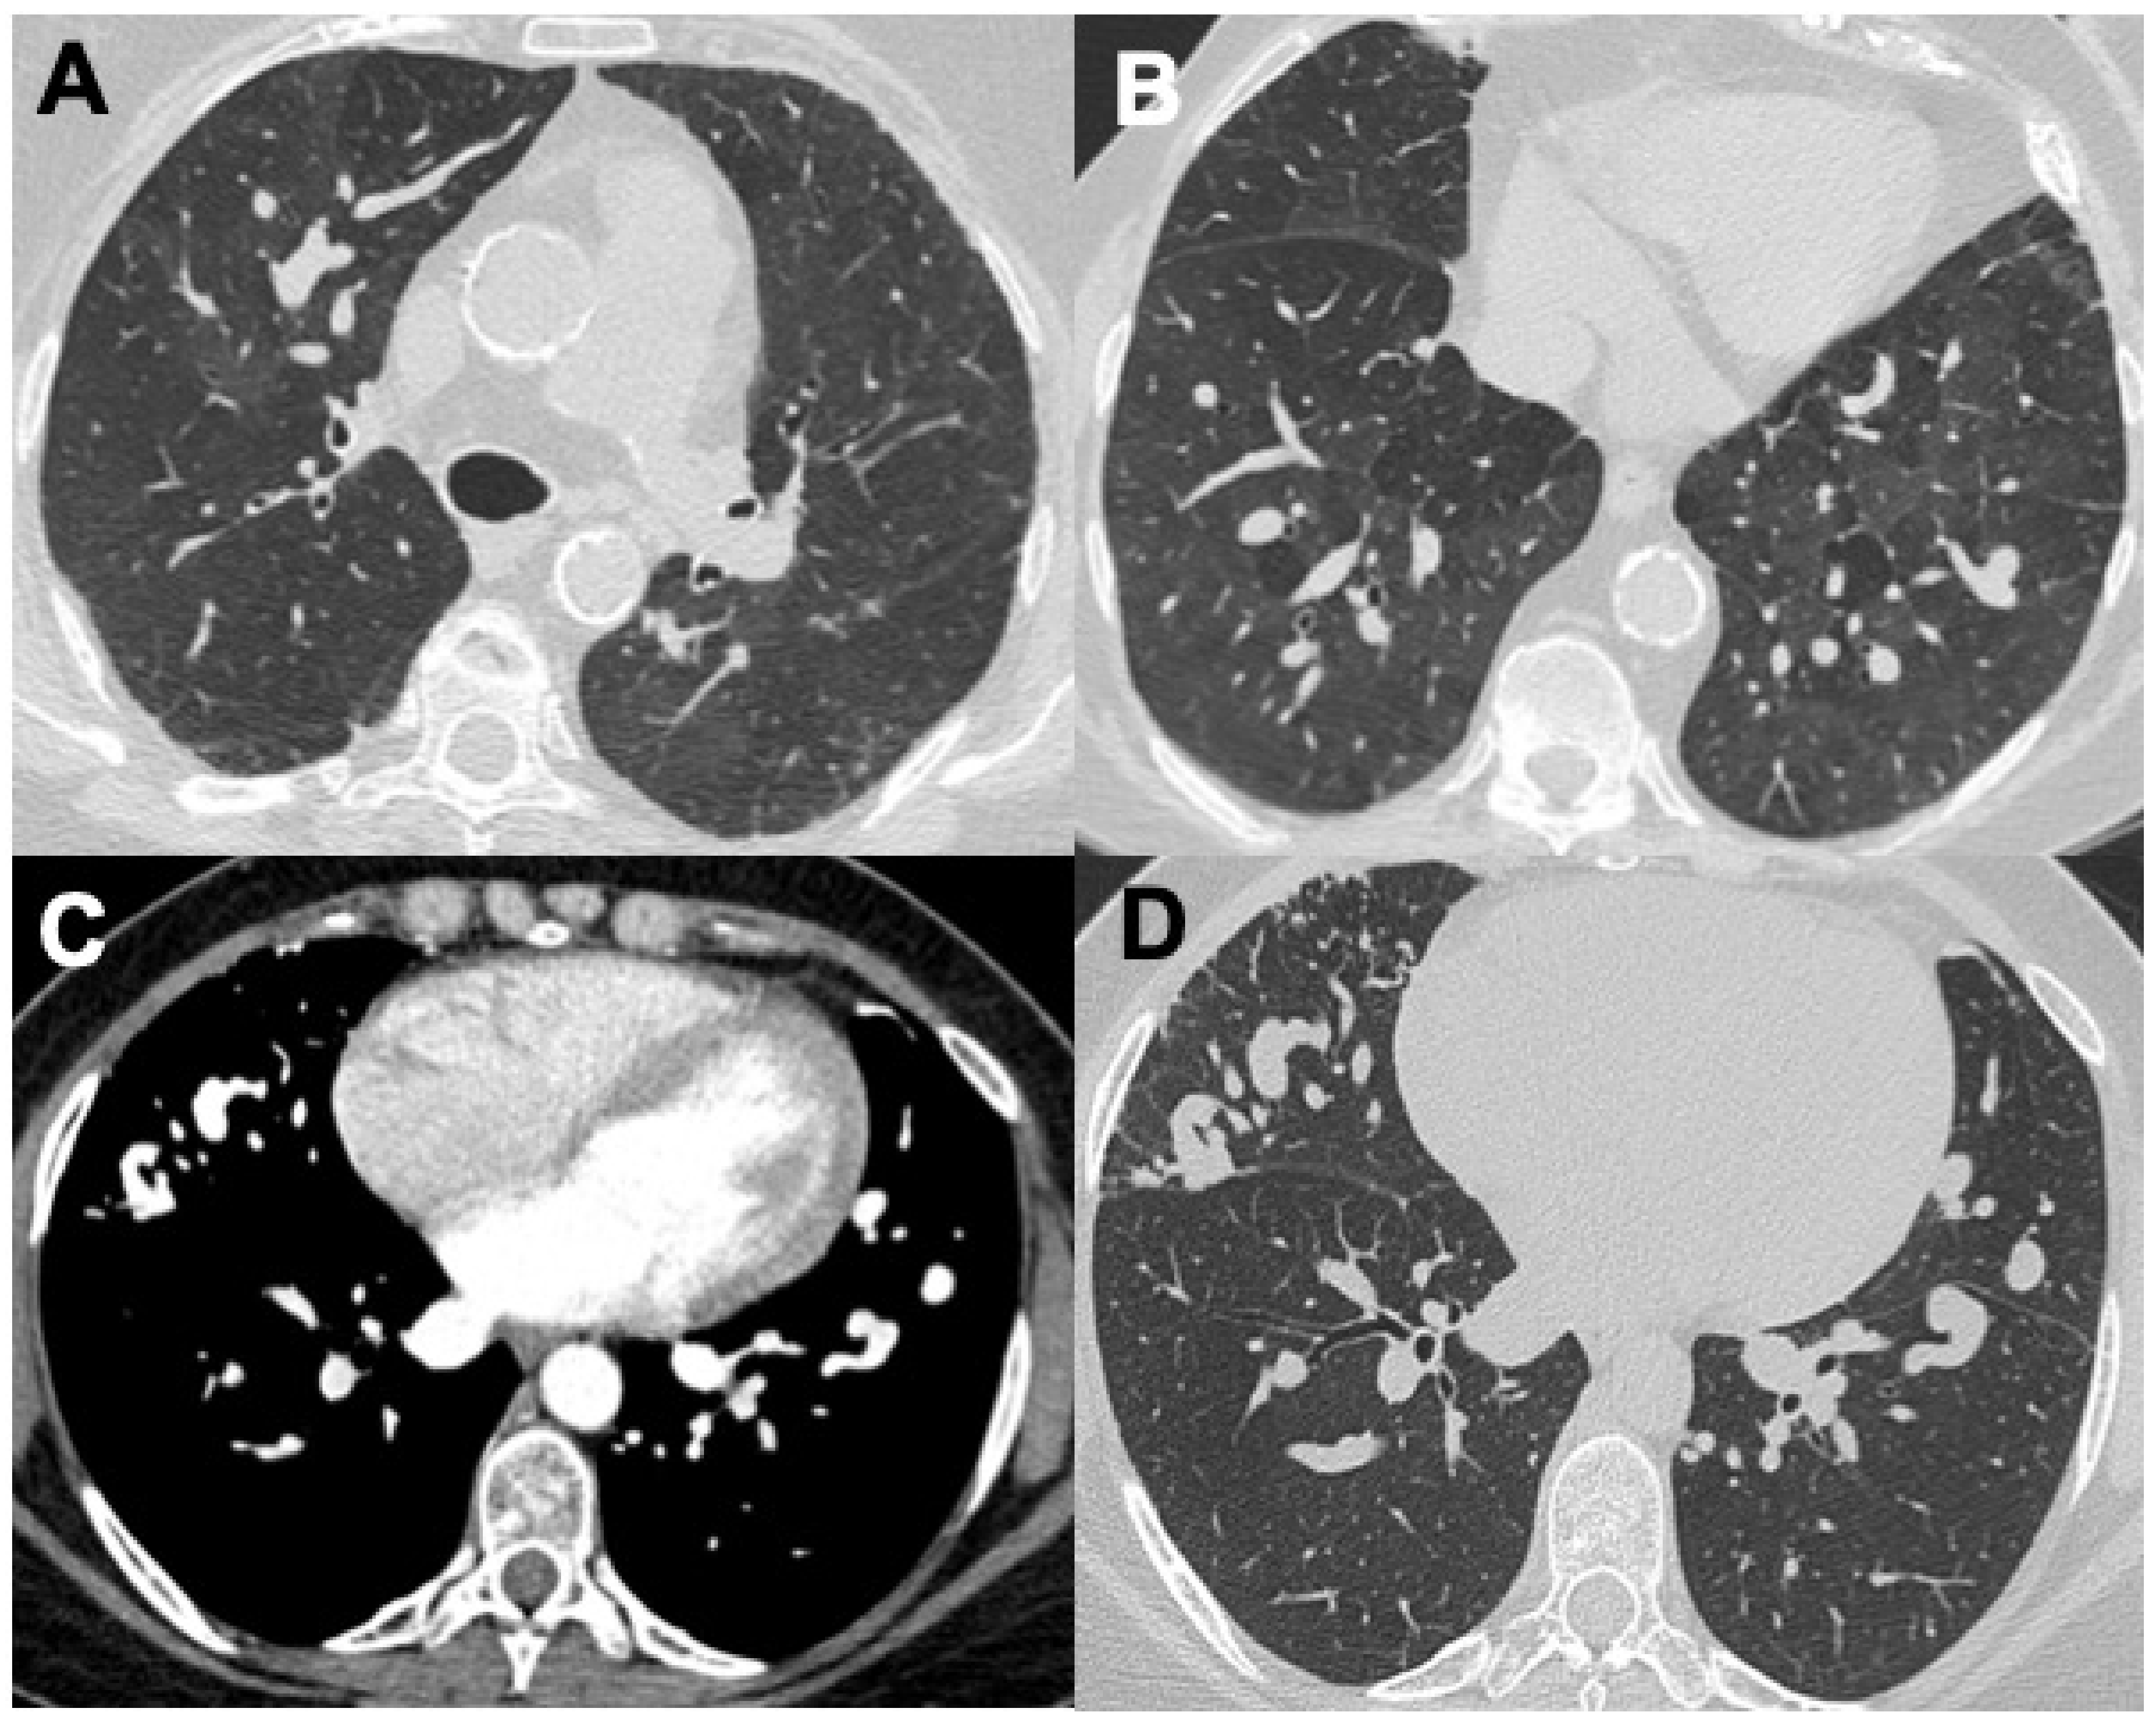

2.3. Granulomatosis with Polyangiitis (GPA)

| GPA | Tracheobronchial involvement (15–55%); bronchiectasis | Nodules (up to 50%); consolidations; GGO (25–50%) and a “crazy-paving” appearance; diffuse alveolar hemorrhage (22–30%) | Pleural effusion (15%); pleuritis; pneumothorax | Pulmonary artery stenosis |